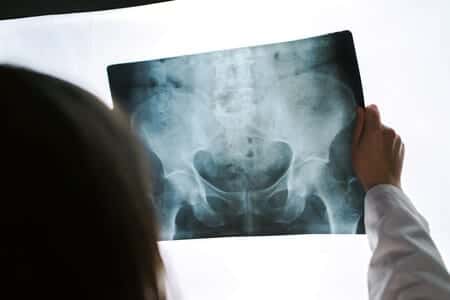

An expert in the use of Stryker hip replacement technology in total hip arthroplasties was required in a medical court case after a patient was diagnosed with lifelong complications from her hip surgery. Her entire right hip had been replaced using Stryker products, but after she awoke from surgery she had lost feeling in most of her leg, developed drop foot with unresponsive foot nerves, and had lost feeling entirely in two of her toes. It was alleged that the sciatic nerve, which spans from the spinal cord down the back of the thigh, had been severely damaged. The woman had also developed a burning pain in the bottom of her foot, and needed a cane and specially designed shoes just to walk.

I do about 50 total hip replacements a year, and have never had a sciatic nerve injury. Although nerve injury is a known complication of the total hip replacement, it tends to be very rare. There may be deviations from the standard of care if the nerve was directly injured or there is evidence of malposition of the components, specifically lengthening, which can lead to nerve injury.